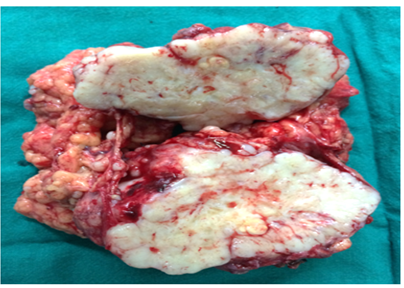

Gross examination of the specimen revealed multiple variably sized nodules studded in the mesenteric fat. The nodules varied in diameter from 0.4 cm to 7.0 cm. Cut-section of these nodules was solid, grey white to grey brown and firm in consistency (Figure 1). On frozen section examination, a diagnosis of metastatic adenocarcinoma was rendered based on clinical and gross findings, clustering of tumour cells, atypical nuclei and myxoid material in the background that was misinterpreted as mucin. Hematoxylin and eosin (H&E) staining on paraffin embedded tissue showed these nodules to be composed of a tumour showing sharply circumscribed aggregates of tumour cells. These aggregates varied in size and shape from being singly scattered to tiny clusters to irregularly shaped islands. Tumour stroma was desmoplastic and showed areas of myxoid change. The tumour cells were small with round to oval hyperchromatic nuclei, scanty cytoplasm, indistinct cell borders and showed high mitotic activity (Figure 2). Immunohistochemistry showed the tumour cells to have strong cytoplasmic positivity for desmin, vimentin and cytokeratin (Figure 3). Thus, the final histopathological diagnosis made was intra-abdominal desmoplastic small round cell tumour which mimicked metastatic adenocarcinoma.

Figure 1 Gross showing cut section of the mass.